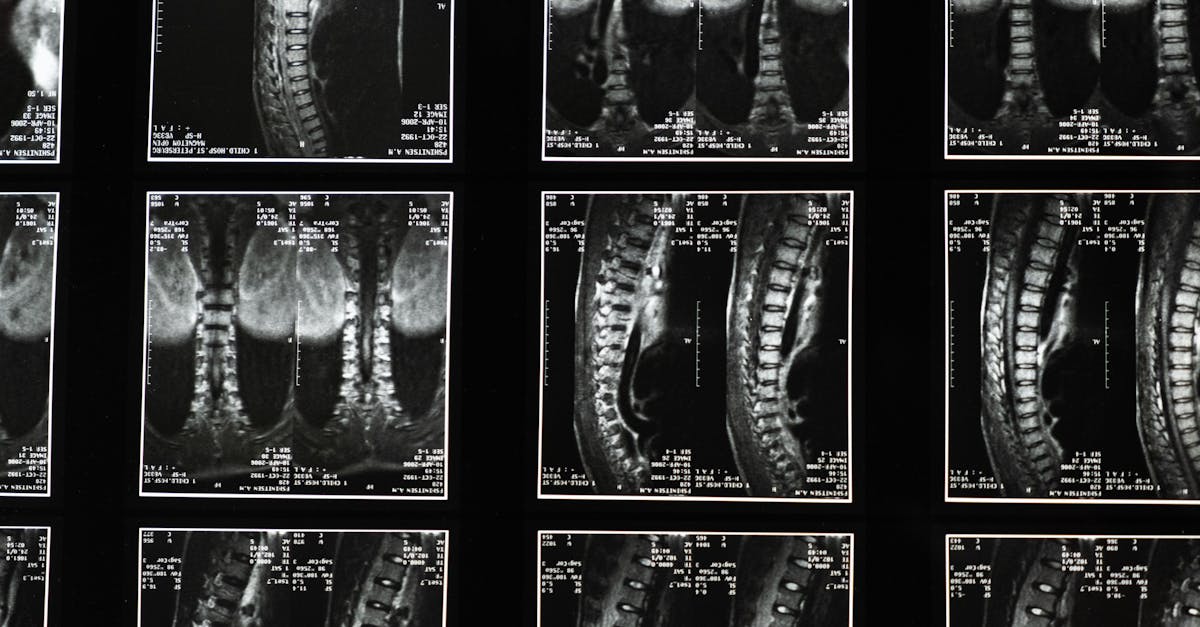

Sciatica, a condition often marked by pain running along the sciatic nerve, can be debilitating. At Pulse Align, we advocate for a holistic approach to lower back pain management, focusing on neuromuscular health, posture improvement, and holistic recalibration. This article delves into effective strategies for sciatica pain relief and lower back pain relief by emphasizing the importance of proper techniques and targeted exercises.

Core strengthening exercises are key to alleviating lumbar pain, particularly for individuals experiencing conditions like herniated discs or spinal stenosis. By enhancing core stability, individuals can improve their posture and distribute weight evenly throughout their body. Exercises such as pelvic tilts and trunk exercises not only alleviate pain but also foster a better alignment which is crucial in preventing future flare-ups.

TAGMED offers an advanced Spinal Decompression Therapy, a non-surgical solution tailored to address moderate-to-severe issues such as herniated discs and spinal stenosis. This specialized technique gently reduces pressure on the affected discs and nerves, aiming to enhance mobility, alleviate back pain, and support your body’s natural healing processes. If you’ve reached a plateau with other therapies, discover how TAGMED’s evidence-based decompression approach can help you resume an active, comfortable life.

TAGMED’s neurovertebral decompression applies a controlled, progressive traction force to the spine, effectively increasing the space between vertebrae. This reduction in pressure on intervertebral discs and nerve roots promotes better fluid circulation in the targeted area. Consequently, this process helps lower inflammation and relieve pain, offering a reliable, non-invasive solution for individuals with chronic back issues. By optimizing fluid movement and nutrient exchange around the discs, patients can experience significant relief from conditions like disc herniation and foraminal stenosis.